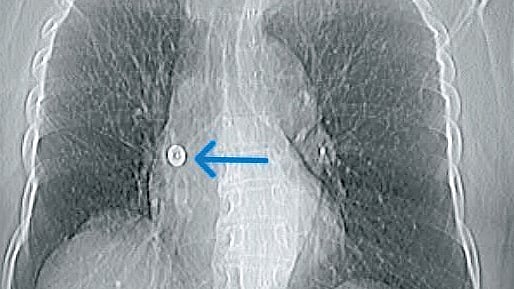

In a rare and complex intervention, doctors retrieved the pin using a minimally invasive bronchoscopic technique involving a Fogarty balloon catheter Photo | Special arrangment

Doctors at Aster CMI took detailed scans, including a chest X-ray and CT scan, which clearly showed the pin stuck inside and attached to the airway wall. Dr Sunil Kumar K, Lead Consultant - Interventional Pulmonologist at the hospital, said the pin’s sharp end had pierced into the lung, making it risky to remove with normal tools. So, the team used a Fogarty balloon to gently move it out and then pulled it out using special forceps, all done while the patient was under sedation.